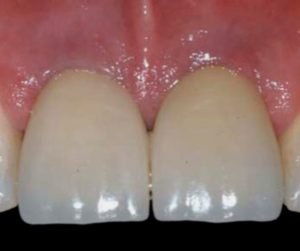

People often assume that the dental implant includes the actual tooth, but this is not the case. The implants are essentially the roots securing new teeth in place. A tooth made of ceramic or Zirconia is attached onto the implant.